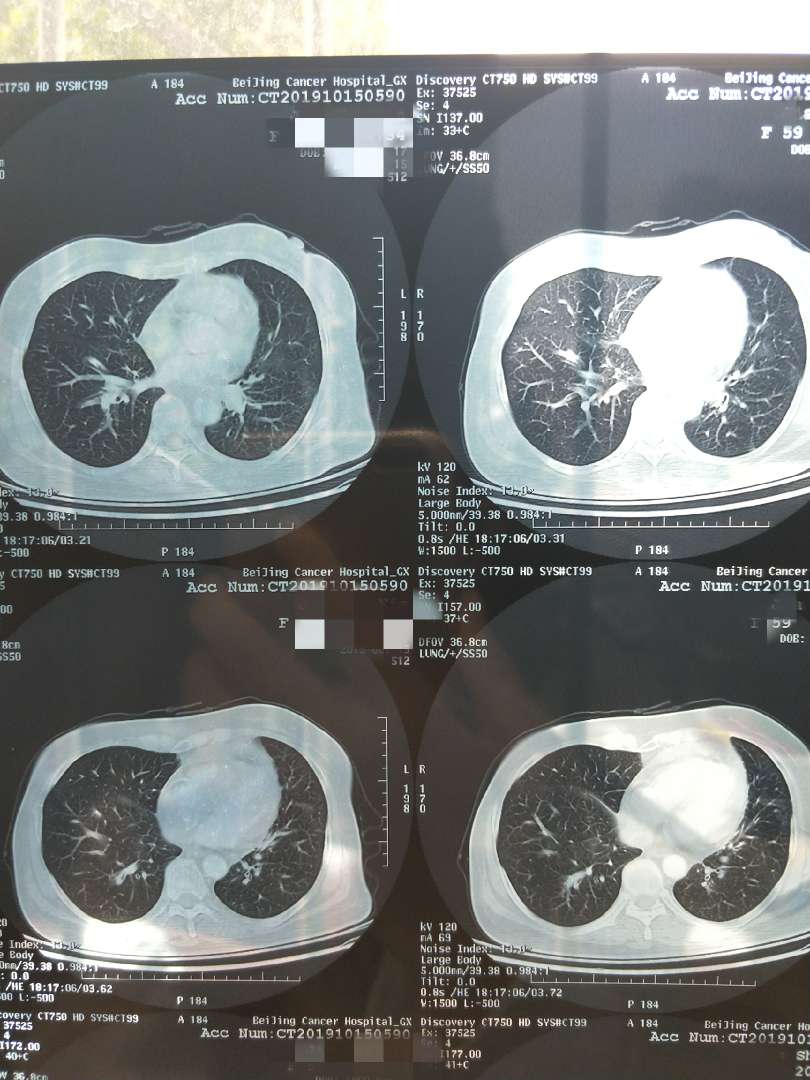

★10.6日左肺下叶结节20*14mm,纵膈多发肿大淋巴结部分融合40*21mm,心包少量积液,左肾上腺占位。

【病理】肺腺癌 ALK–EML4融合